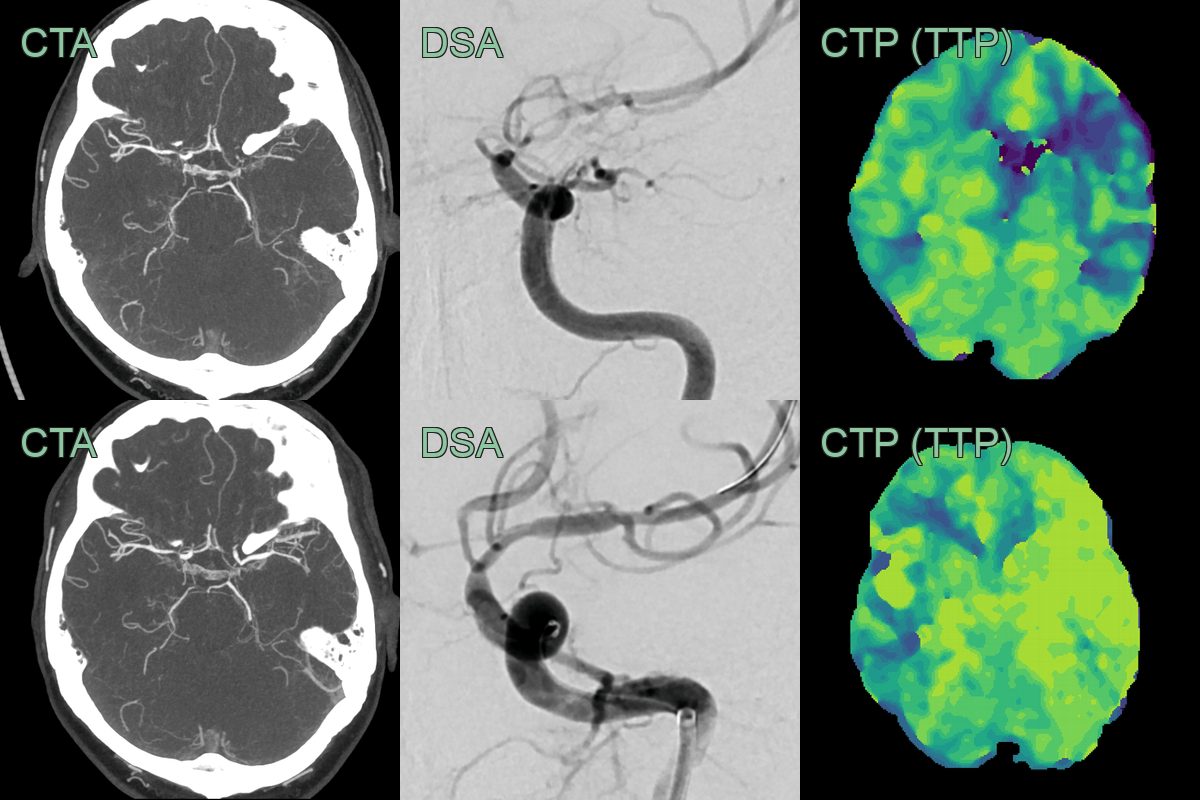

- With worsening perfusion, an angioplasty successfully widened the stenosis and significantly improved perfusion.